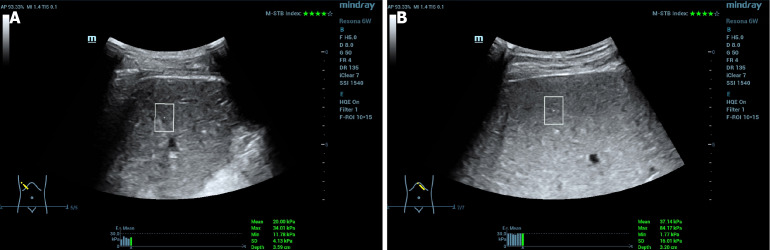

Methods: A total of 76 patients with liver cirrhosis and portal hypertension who underwent TIPS were included. Liver and spleen stiffness was assessed using the sound touch quantify (STQ) value, determined via point shear wave elastography in ultrasound imaging. Cox regression analysis was employed to evaluate the relationship between liver and spleen stiffness and cumulative survival in TIPS patients.